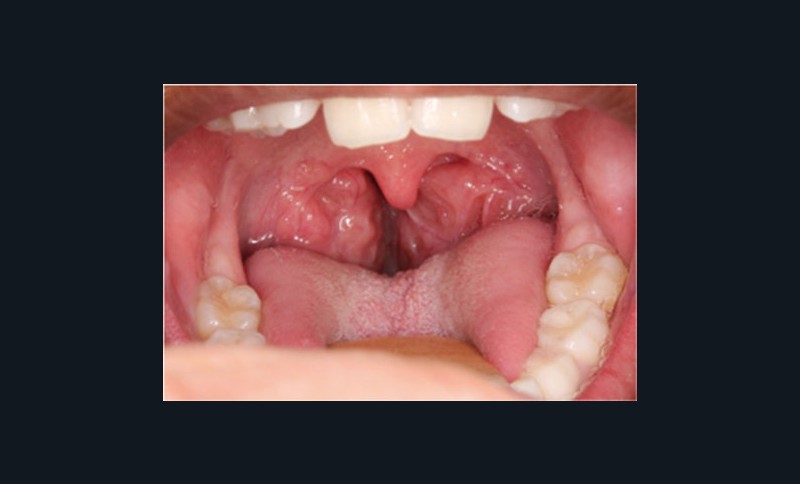

– les enfants présentant un obstacle ORL (les plus nombreux) : typiquement, il s’agit d’une hypertrophie des amygdales (tonsilles) palatines (fig. 1) ;